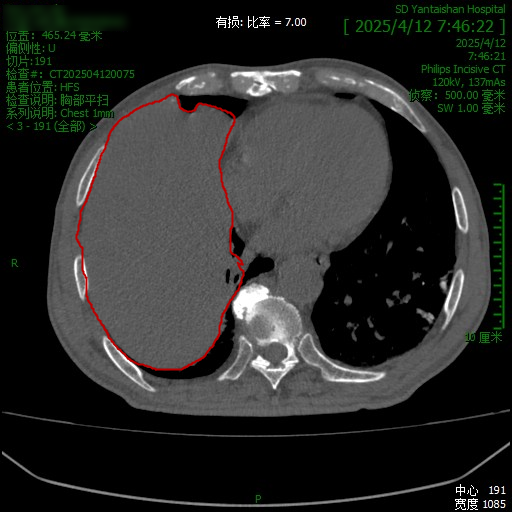

在烟台山医院东院心胸外科,患者接受了相应的影像学检查,其右肺存在巨大肿块,周围肺组织受压膨胀不全。为此,费秀渠主任医师、王大伟副主任医师团队认真评估患者当前病情,请内分泌科专家会诊,并制定了相应的手术方案。

图中所示为患者右肺的巨大肿块。